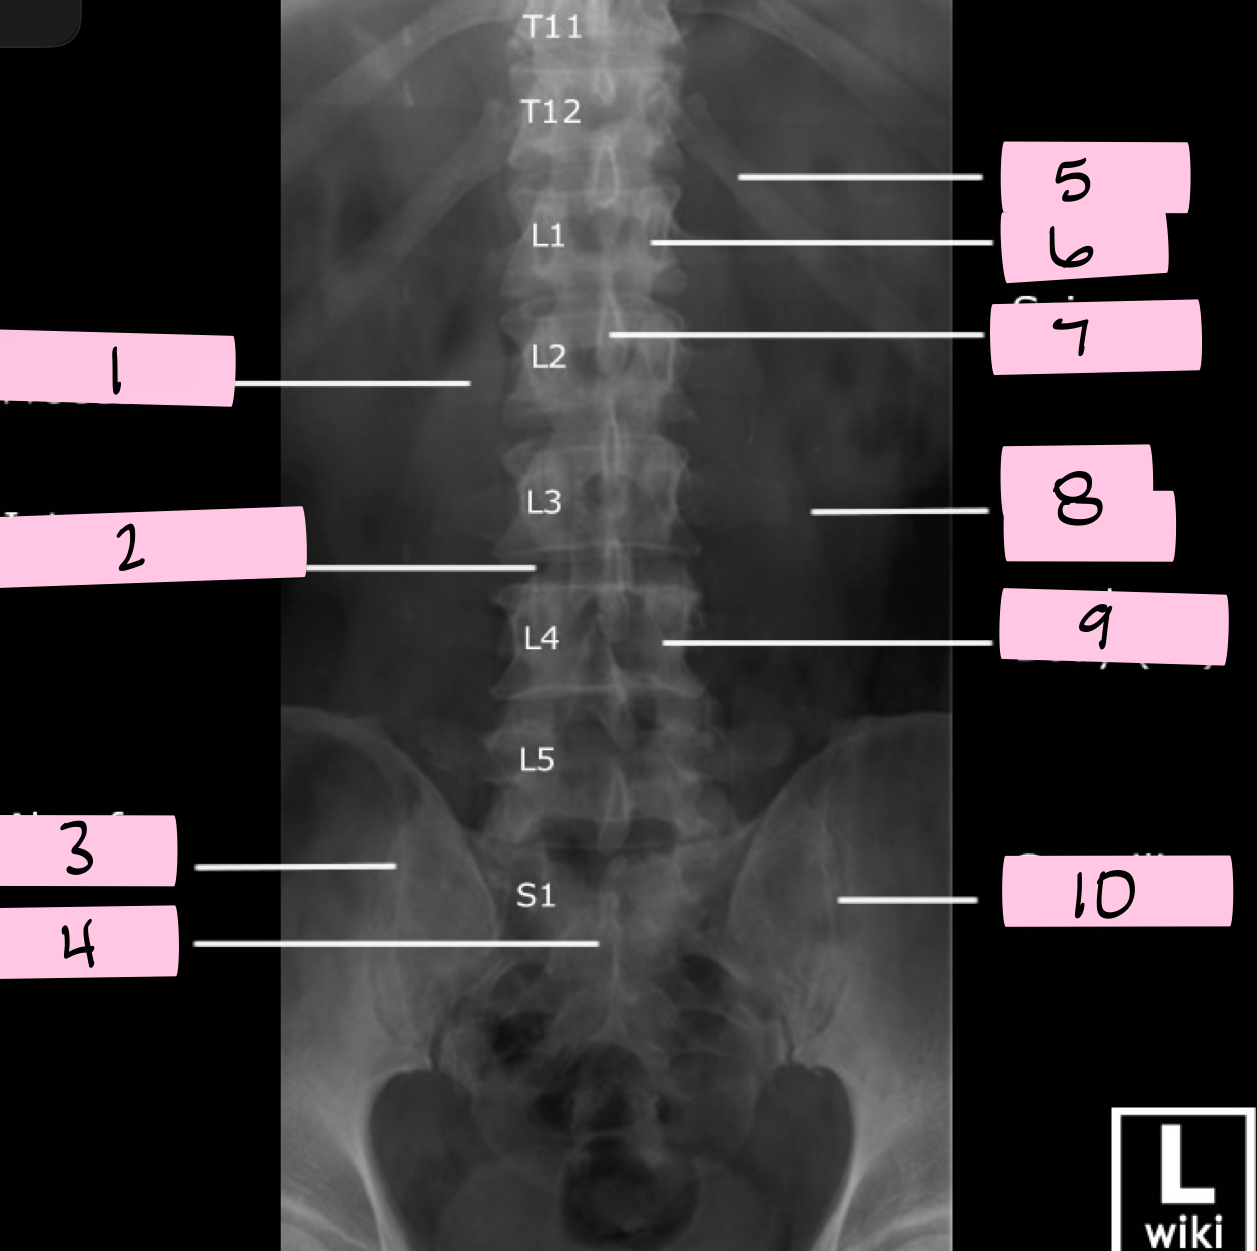

What is 1 pointing to?

Transverse process

What is 2 pointing to?

Intervertebral disk

What is 3 pointing to?

Ala of sacrum

What is 4 pointing to?

Sacrum

What is 5 pointing to?

12th Rib

What is 6 pointing to?

Pedicle

What is 7 pointing to?

Spinous process

What is 8 pointing to?

Psoas muscle

What is 9 pointing to?

Lumbar body (L4)

What is 10 pointing to?

Sacroiliac joint